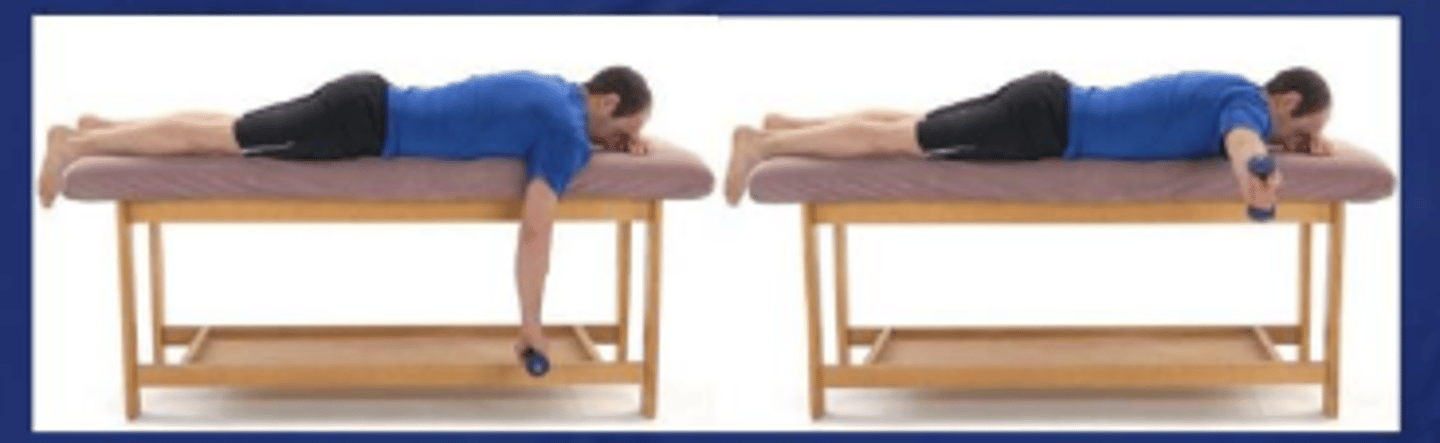

Prone horizontal abduction with full ER, 100° abduction

What does the image show?